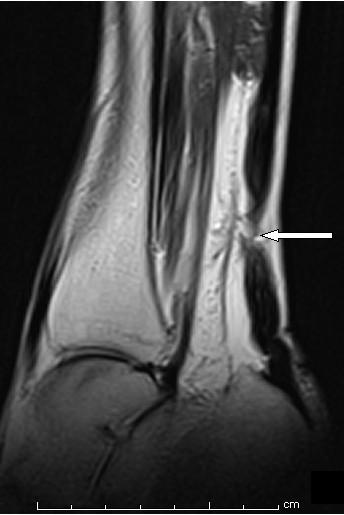

A 78-year-old Caucasian woman presented with spontaneous non-traumatic bilateral rupture of the Achilles tendons. Her symptoms started two days after she took ciprofloxacin 500 mg twice daily for a urinary tract infection and prednisolone 30 mg once daily for chronic obstructive airway disease.

一名78岁的白种女性出现自发性非创伤性双侧跟腱断裂。她在每天两次服用500毫克环丙沙星治疗尿路感染以及每天一次服用30毫克泼尼松龙治疗慢性阻塞性气道疾病两天后开始出现症状。